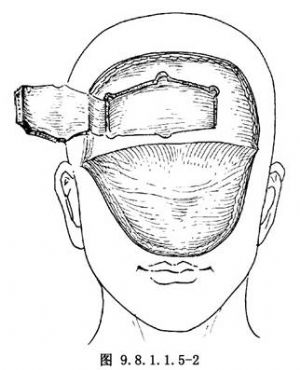

(3)翻瓣:切口完成後,向前下翻開軟組織瓣。組織瓣內包括皮膚及腱膜。雙側顳部在顳肌膜外翻轉,下方翻至眶上緣,注意保護眶上神經及血管(圖9.8.1.1.5-2)。

(4)額骨瓣製作:根據手術需要,製作單側或雙側額骨瓣。以一側爲主跨中線骨瓣爲例。主瓣側鑽4個孔,對側鑽2個孔。骨瓣下線距眶緣1.5~2cm。此較腦外科開顱下線要低,其目的在於方便顱底操作,減輕腦組織牽引,減少修復顱底的腱膜長度。因下方切開線較低,多有額竇暴露。由於本術式設計有腱膜瓣折翻到顱底,暴露之竇腔可以得到可靠的封閉。鑽孔完成後,經骨窗可用剝離子仔細分離兩孔間硬腦膜,中線處要特別注意,勿損傷矢狀竇。兩孔間用Gigli線鋸鋸開。鋸開線方向宜讓骨板緣有一定斜度,以利骨瓣復位時固位。完成鋸開線後,宜用剝離子順四周骨鋸開線再分離硬腦膜一次,然後輕抬骨瓣。遇有連接處要仔細分離,避免猛揭骨瓣,撕裂硬腦膜(圖9.8.1.1.5-2)。